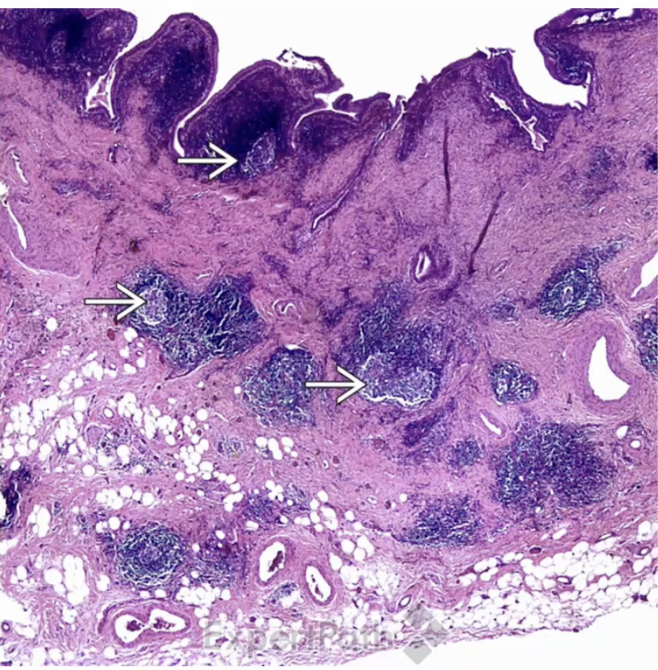

Follicular Cholecystitis

Adenocarcinoma of the Gallbladder